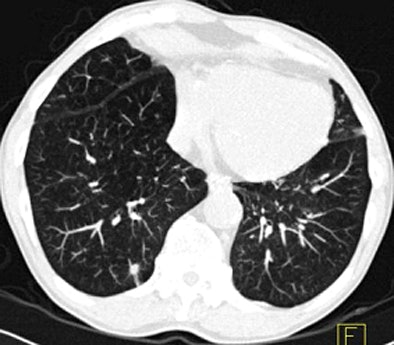

| Images above and below show a spiculated nodule measuring 169 mm3 at baseline low-dose CT screening. Bottom image, acquired four years after the baseline scan, shows that the nodule has resolved. All images courtesy of Dr. Rosemarijn Vliegenthart. |